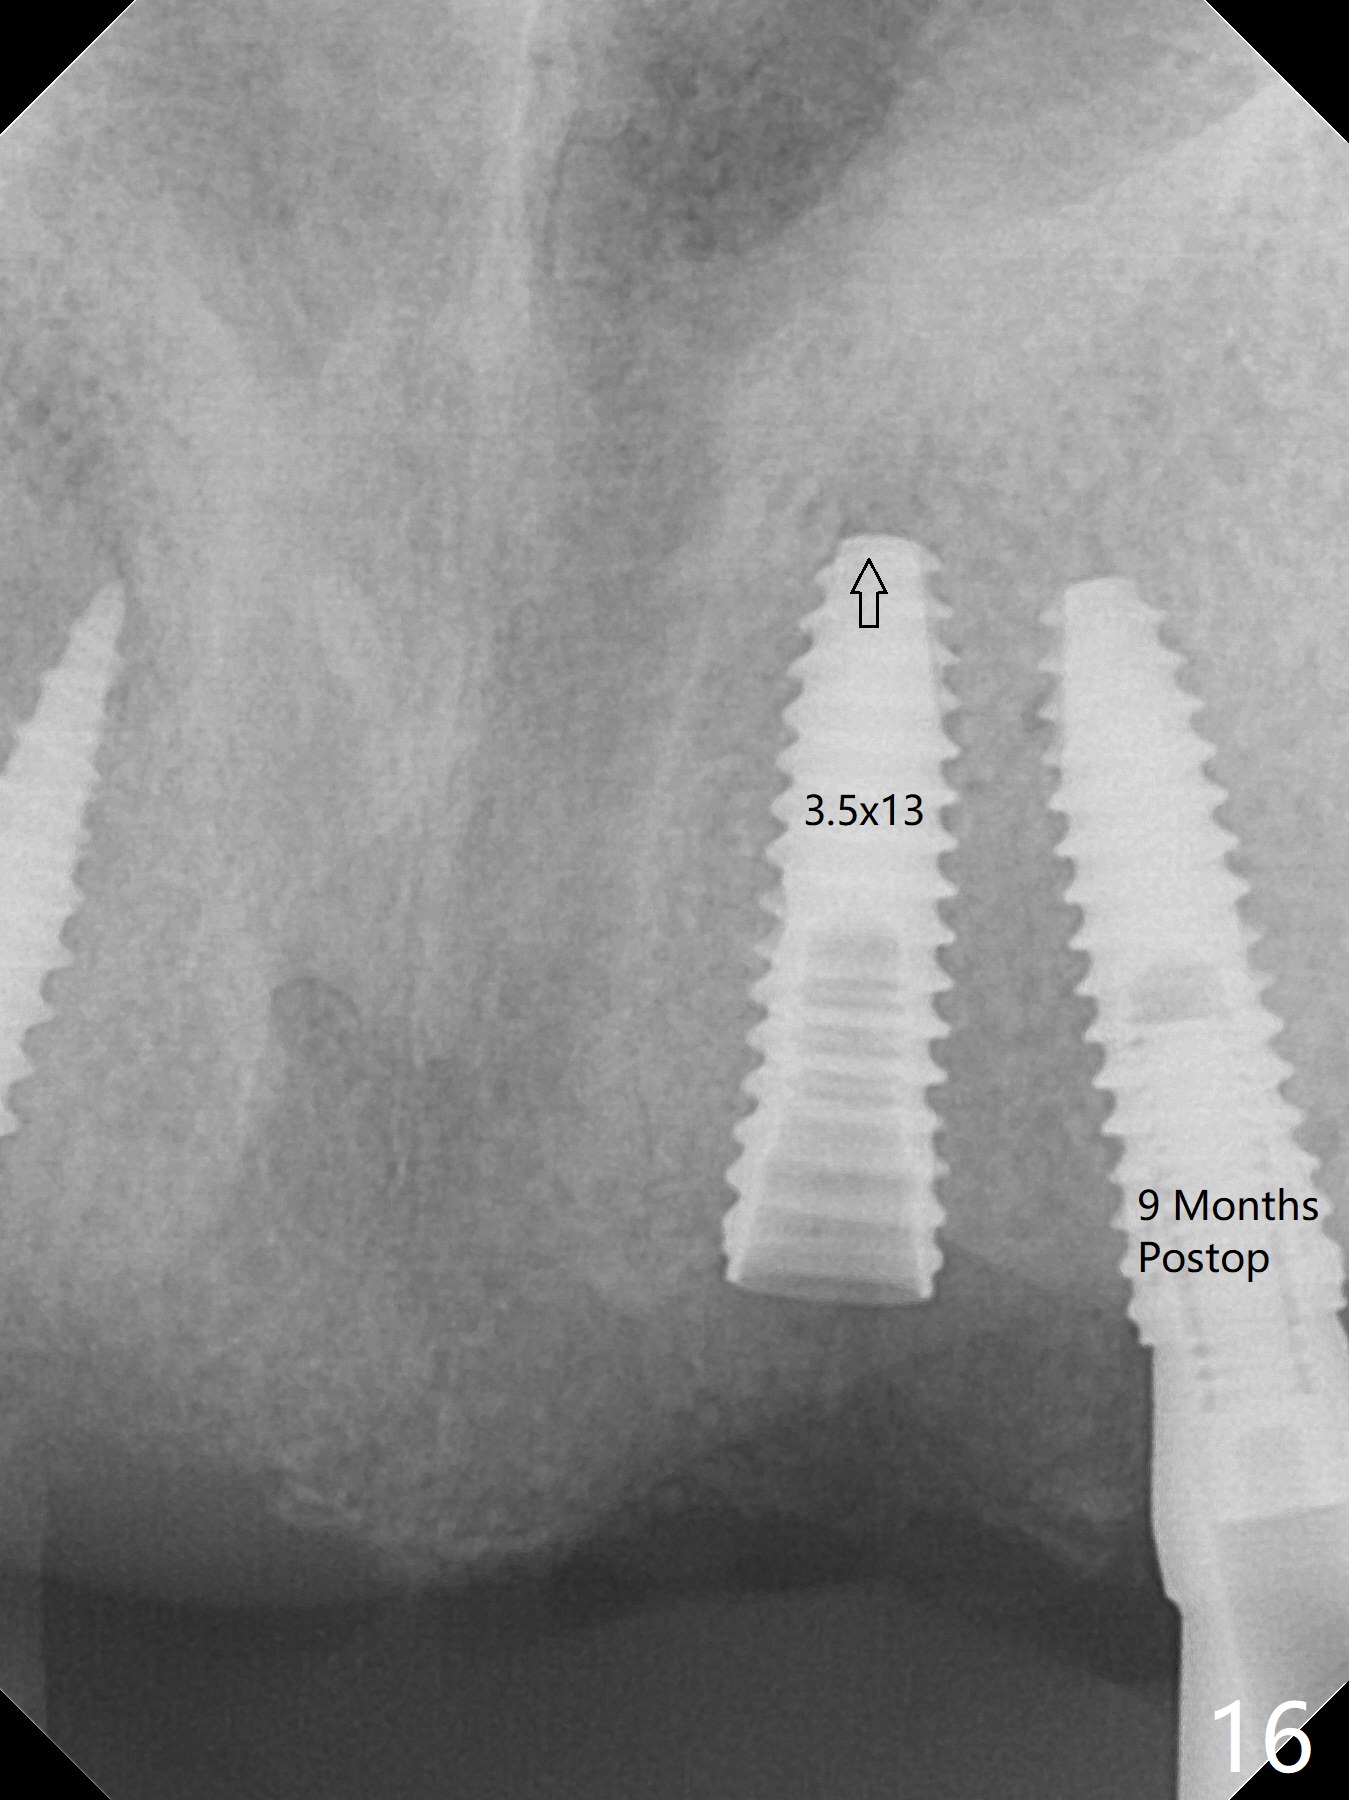

To have enough clearance for the splinted provisional at #6-12 (Fig.1 *), composite has been placed in the posterior teeth (bilateral, *, Fig.2). When the composite is removed, there is no clearance between the implants/abutments of #7 or 10 (Fig.3). Incision is made with removal of the 1-piece implant at #7; there is enough bone to move the osteotomy buccal (Fig.4 arrowhead). When the same implant is placed buccal (Fig.5), there is sufficient clearance for restoration (Fig.6 *), while there is still enough buccal bone left (Fig.7). When the patient returns 5.5 (for #7 and 10)/6.5 (#6,11,12) months postop, his chief complaint is tenderness lingual to #11. In fact, the abutment screw is loose at #11, while the implant at #10 has mobility (Fig.8), which is related to loss of the posterior stops (*) due to wear. There is slight bone loss mesial to #10 implant 5.5 months postop (Fig.10, as compared Fig.9). CBCT taken 5.5/6.5 months postop shows no bone loss (Fig.11-15). The 3x14 mm 1-piece implant at #10 is mobile 9 months postop and is removed and replaced by a 3.5x13 mm 2-piece one with slightly buccal osteotomy (Fig.16). PAs are taken prior to impression (Fig.17,18). The abutment at #12 is loose (<). More composite needs to be added to the occlusal surface of the upper posterior teeth. Finally the patient agrees to have crowns for the upper posterior teeth.